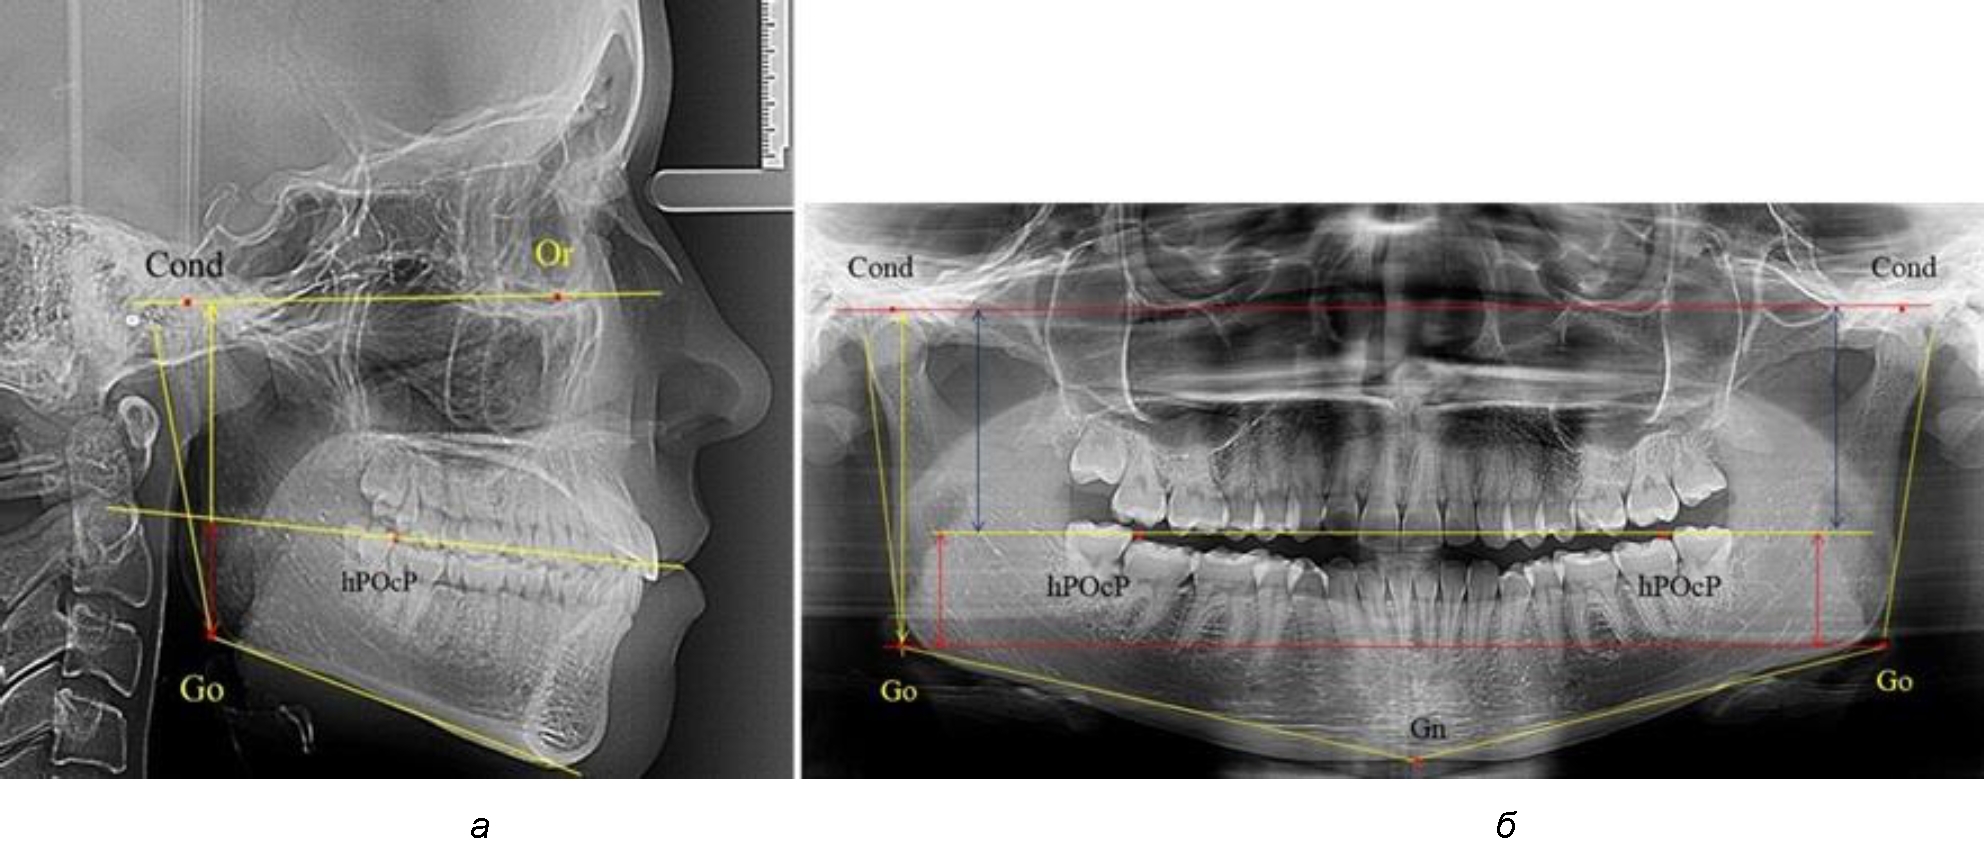

На боковых телерентгенограммах определяли положение верхней точки суставной головки Cond. Касательные линии к ветви и телу нижней челюсти пересекались в точке, которую в клинической практике обозначают как точка угла нижней челюсти или точка гонион Go. Точкой hPOcP обозначали дистальный бугорок нижнего второго моляра вблизи окклюзионного контура коронки, через нее от межрезцовой точки проводили окклюзионную линию, ее продолжали до задней части ветви челюсти. Высоту ветви измеряли как расстояние от угла нижней челюсти до вершины суставной головки Go-Cond. Общую высоту ветви условно делили на 2 части, ее границей служила окклюзионная линия. Верхнюю часть обозначали как окклюзионно-суставная, а нижнюю – как окклюзионно-гониональная.

Рис. 1. Метод измерения высоты ветви нижней челюсти на телерентгенограмме (а) и ортопантомограмме (б)